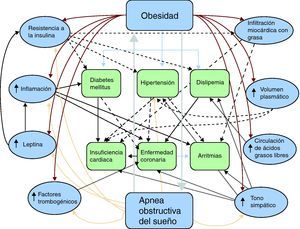

Fisiopatología de la obesidad y enfermedad cardiovascularLa asociación entre obesidad y diferentes formas de enfermedad cardiovascular es compleja, probablemente debido a los diferentes mecanismos fisiopatológicos que involucran gran cantidad de factores e interactúan de una manera enmarañada (Figura 1). La obesidad puede causar aterosclerosis coronaria a través de mecanismos bien descritos y aceptados, tales como dislipemia, hipertensión y diabetes mellitus tipo 25,6. Sin embargo, la evidencia reciente ha demostrado que la asociación entre obesidad y enfermedad cardiovascular7 podría incluir muchos otros factores, como inflamación subclínica, activación neurohormonal con aumento del tono simpático8, altas concentraciones de leptina e insulina9, AOS e intercambio aumentado de ácidos grasos libres, y también debido al depósito de grasa en áreas específicas del cuerpo con función directa en la patogeia de la aterosclerosis coronaria, como la grasa subepicárdica (Tabla 1)10.

Figura 1. Fisiopatología de la obesidad y la enfermedad cardiovascular. Los diferentes mecanismos fisiopatológicos por los cuales se asocia la obesidad a la enfermedad cardiovascular son complejos y no se limitan a factores como la diabetes mellitus tipo 2, la hipertensión o la dislipemia. También se han descrito factores que interactúan de manera indirecta, como la inflamación subclínica, la activación neurohormonal con aumento del tono simpático, las altas concentraciones de leptina e insulina, la apnea obstructiva del sueño, el intercambio aumentado de ácidos grasos libres y el depósito de grasa intramiocárdico y subepicárdico.